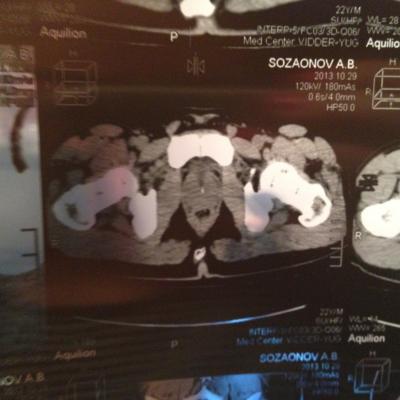

проведена МСКТ области таза!Внеорганных дополнительных патологических образований,лимфаденопатии или свободной жидкости в области таза не выявлено.

Мочевой пузырь-наполнен,стенки не утолщенны,паравезикально-без грубой органки.

Граница между предстательной железой и пузырем несколько четкая,контур пузыря на данном уровне не деформирован.

Предстательная железа-без грубой органики,еденичные микрокальцинаты.

Семенные пузырьки-конфигурация не совсем типична,примерный размер правого 26*28мм.Отмечаются признаки кистовидной трансформации и микрокальцинации обоих пузырьков.Наибольшая из кист слева достигает 9 мм.Обращает на себя внимание неравномерная кальцинация стенок крупных регионарных(текстикулярных)артерий с обоих сторон.

Заключение:на момент исследования,КТ-данных за наличие внеорганных дополнительных патологических образований,лимфоденопатии или свободной жидкости в области таза не выявлено.КТ-признаки в пользу проявлений калькулезного везикулита с элементами кистовидной трансформации семенных пузырьков.